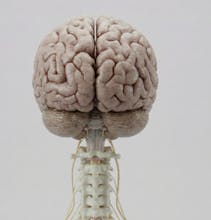

Natomy AI creates high-quality, medically accurate images and videos of human anatomy. Start with image-to-image: upload any low-quality photo, real image, or animation, and Natomy transforms it into an ultra-realistic anatomical visual. Unlike other AI tools that get anatomy wrong, Natomy is accurate every time—and fully editable by simply highlighting what you want changed and describing the update. Text-to-video launches in 2 weeks.